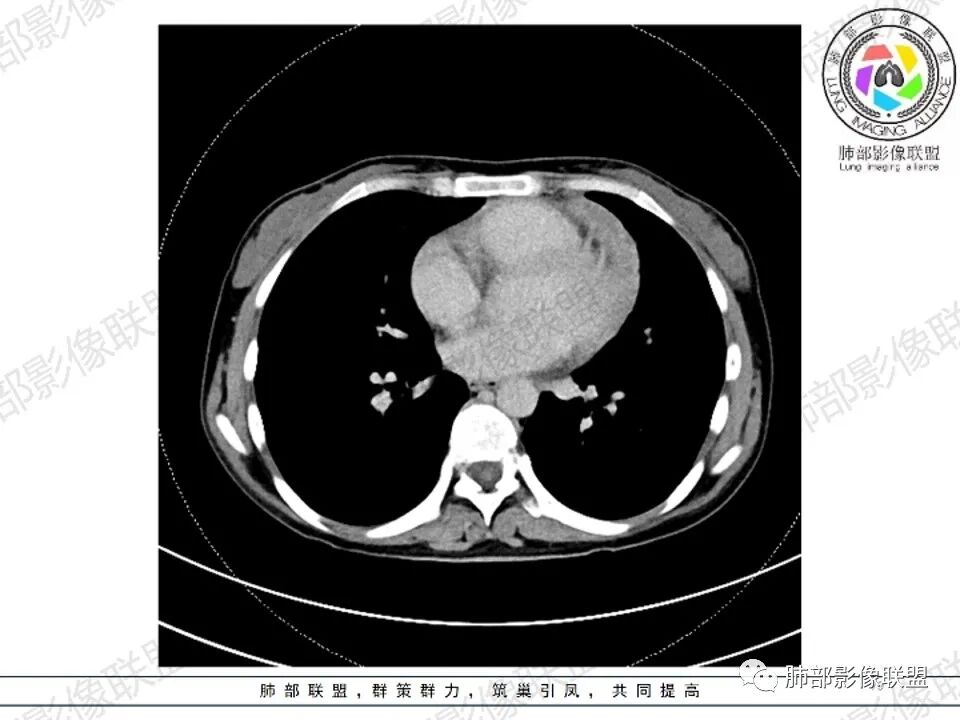

2.影像显示前纵隔不规则块状影,依势贴附心脏大血管旁,密度不均,边界不甚清楚,有结节融合感。

3.病灶轻度不均匀强化,可见血管穿行,散在液性低密度区。

双肺门未见肿大淋巴结。

4.双侧腋窝区见增大淋巴结,边界清楚。

1.年轻女性,前纵隔不规则块状影,密度不均,边界不甚清楚,有结节融合感,轻度不均匀强化,可见血管穿行,最常见最符合的无疑是淋巴瘤!